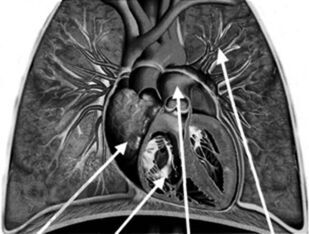

Аннотация

Монография посвящена проблемам диагностики и лечения легочной гипертензии. Термином «легочная гипертензия» объединяют группу нозологий с общим диагностическим критерием — повышением давления в легочной артерии. В работе представлены вопросы патогенеза и генетические основы легочной гипертензии, дана ее современная классификация, описаны формы легочной артериальной гипертензии, легочной гипертензии вследствие патологии левых отделов сердца, легких или хронической тромбоэмболии легочной артерии. Дан диагностический алгоритм, включающий оптимальные методы диагностики. Монография представляет современные возможности лечения легочной гипертензии, знакомит с данными ключевых рандомизированных клинических исследований и позволяет заглянуть в будущее. Работа создана специалистами ведущих экспертных центров нашей страны во главе с ФГБУ «Российский кардиологический научно-производственный комплекс» МЗ РФ и предназначена для кардиологов, пульмонологов, терапевтов, ревматологов, а также для практикующих врачей, имеющих отношение к обследованию и лечению больных с легочной гипертензией.